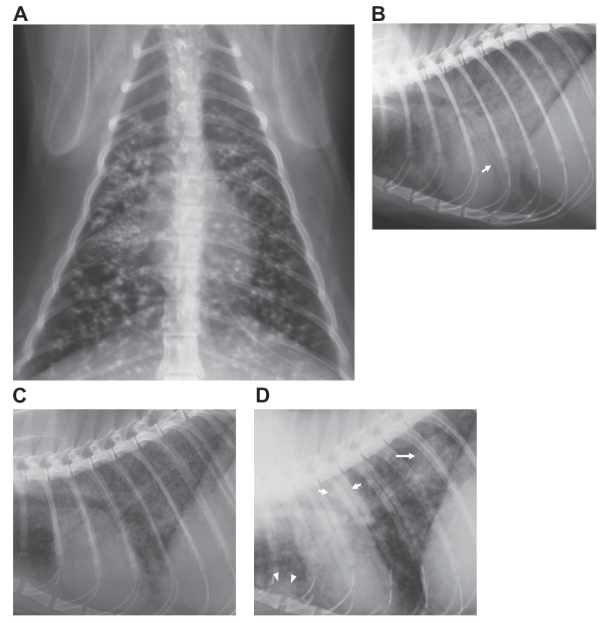

Regarding radiographic changes associated with mycobacterium infection in cats (Bennett, 2011 JFMS):

Bennett, A.D., Lalor, S., Schwarz, T., et al. (2011) Radiographic Findings in Cats with Mycobacterial Infections. Journal of Feline Medicine & Surgery 13, 718–724